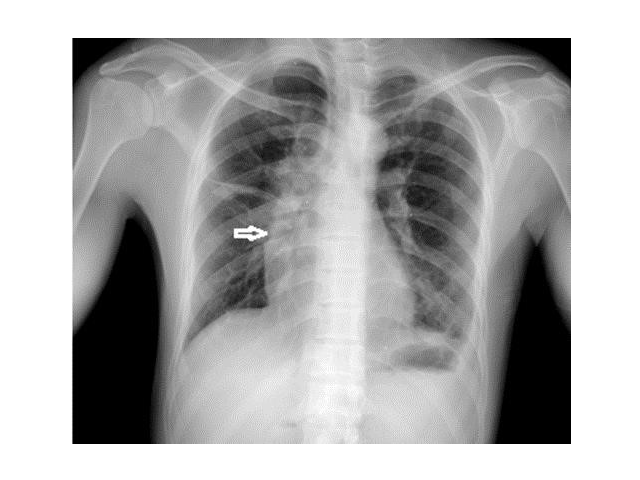

Hematomediastinum caused by mediastinal injury is often found to be difficult to diagnose until clinical presentation, and no cases of delayed onset have been reported. A 35-year-old patient who developed mediastinal hematoma 9 days after presentation was treated. Radiography and CT scan were used for diagnosis and hematoma was removed by mediastinal puncture.